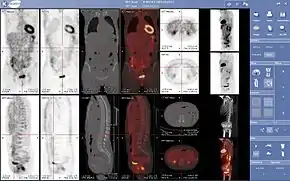

Combination of PET with CT or MRI

PET scans are increasingly read alongside CT or magnetic resonance imaging (MRI) scans, with the combination (called "co-registration") giving both anatomic and metabolic information (i.e., what the structure is, and what it is doing biochemically). Because PET imaging is most useful in combination with anatomical imaging, such as CT, modern PET scanners are now available with integrated high-end multi-detector-row CT scanners (so-called "PET-CT"). Because the two scans can be performed in immediate sequence during the same session, with the patient not changing position between the two types of scans, the two sets of images are more precisely registered, so that areas of abnormality on the PET imaging can be more perfectly correlated with anatomy on the CT images. This is very useful in showing detailed views of moving organs or structures with higher anatomical variation, which is more common outside the brain.

For brain imaging, registration of CT, MRI and PET scans may be accomplished without the need for an integrated PET-CT or PET-MRI scanner by using a device known as the N-localizer.[22][65][66][67]